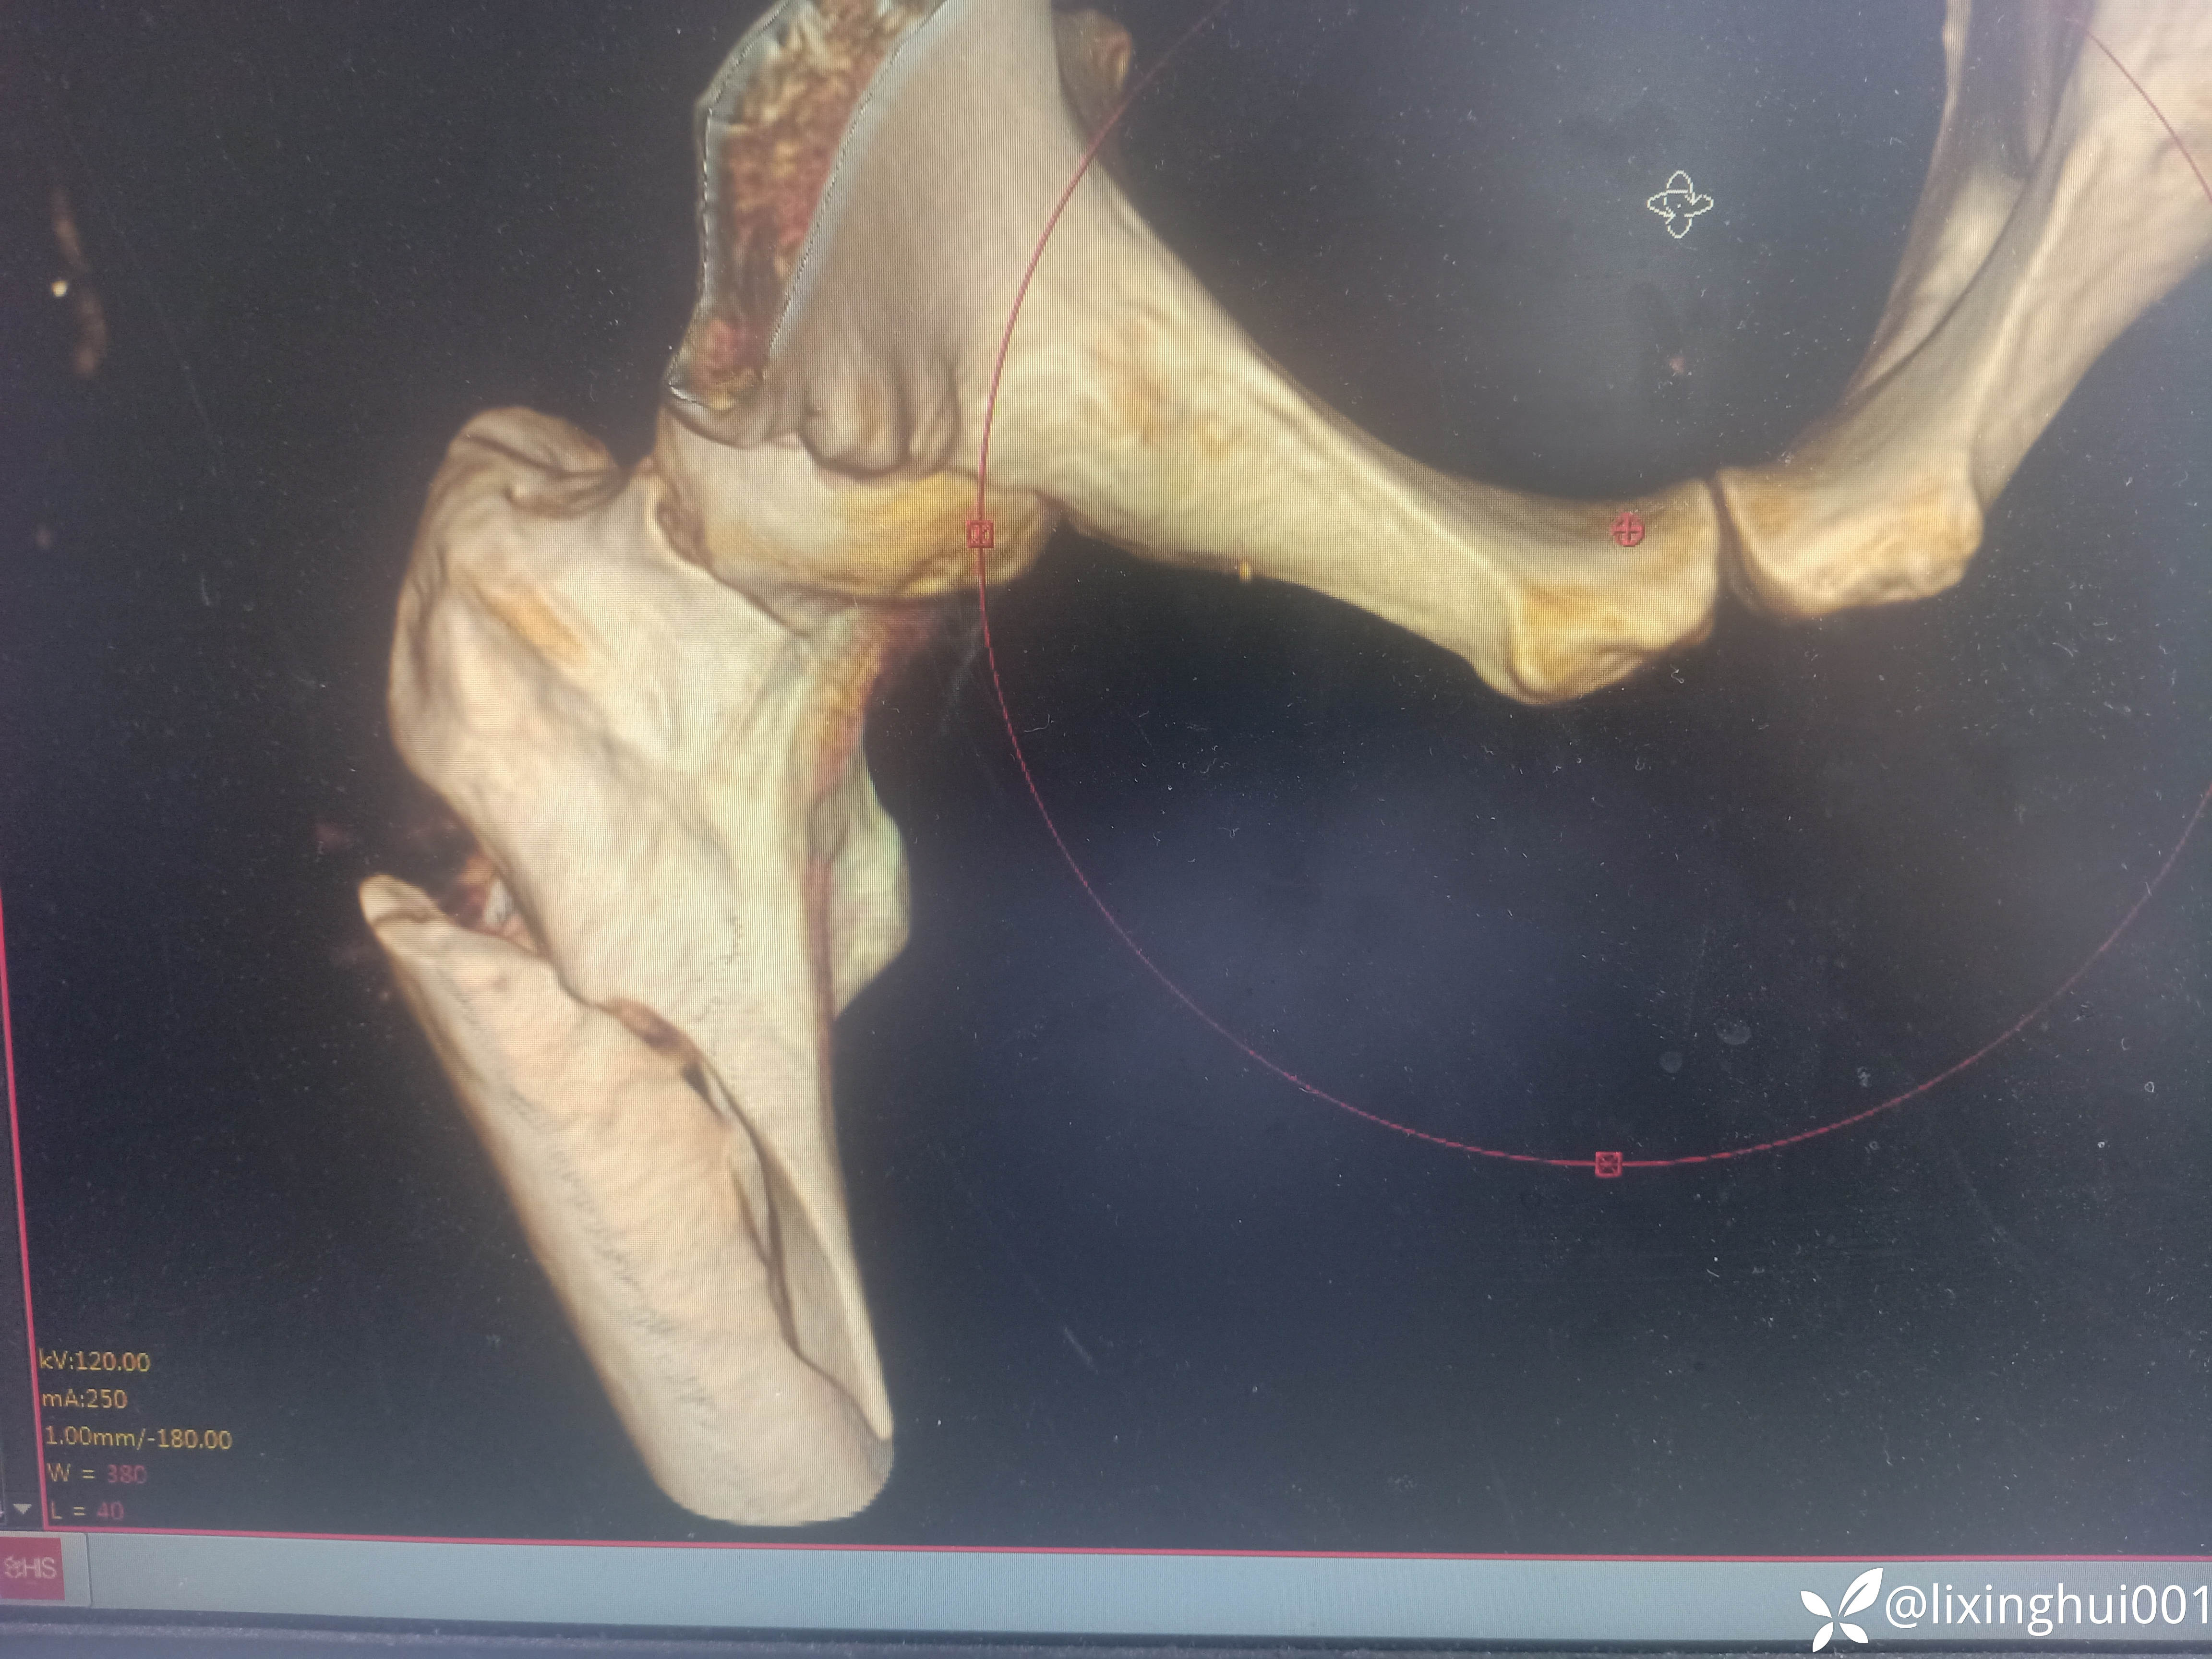

56岁股骨颈骨折术后股骨近端再次骨折

【患者信息】:56岁男性,40天前因右股骨颈骨折于外院行闭合复位螺钉内固定术,不慎再次摔伤来诊

【临床诊断】:右股骨颈骨折术后,→股骨近端骨折

考虑患者年轻,没有股骨头坏死,暂时予以内固定治疗,术后发生股骨头坏死,再行置换。要是年龄较大,同时股骨头有坏死发生,一期加长柄置换是否可行。